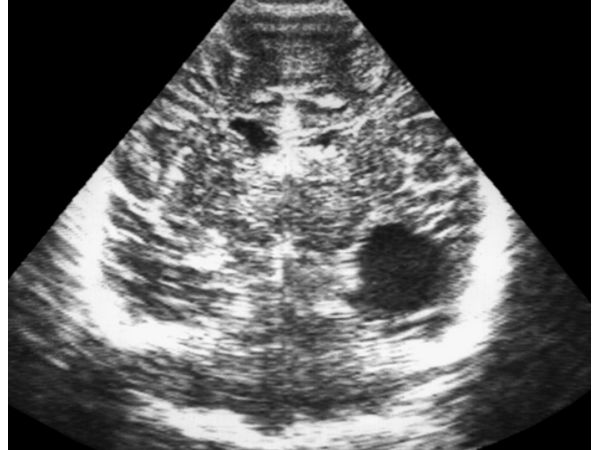

На фоне проведённого оперативного и медикаментозного лечения неврологическая симптоматика регрессировала, судорожные приступы купированы. При контрольном осмотре пациентки через четыре недели после операции была выявлена сформированная внутримозговая киста в височной доле правого полушария размерами 23х20х25мм с чётким контуром и однородным содержимым.